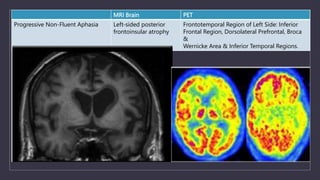

MRI Brain PET

Progressive Non-Fluent Aphasia Left-sided posterior

frontoinsular atrophy

Frontotemporal Region of Left Side: Inferior

Frontal Region, Dorsolateral Prefrontal, Broca

&

Wernicke Area & Inferior Temporal Regions.